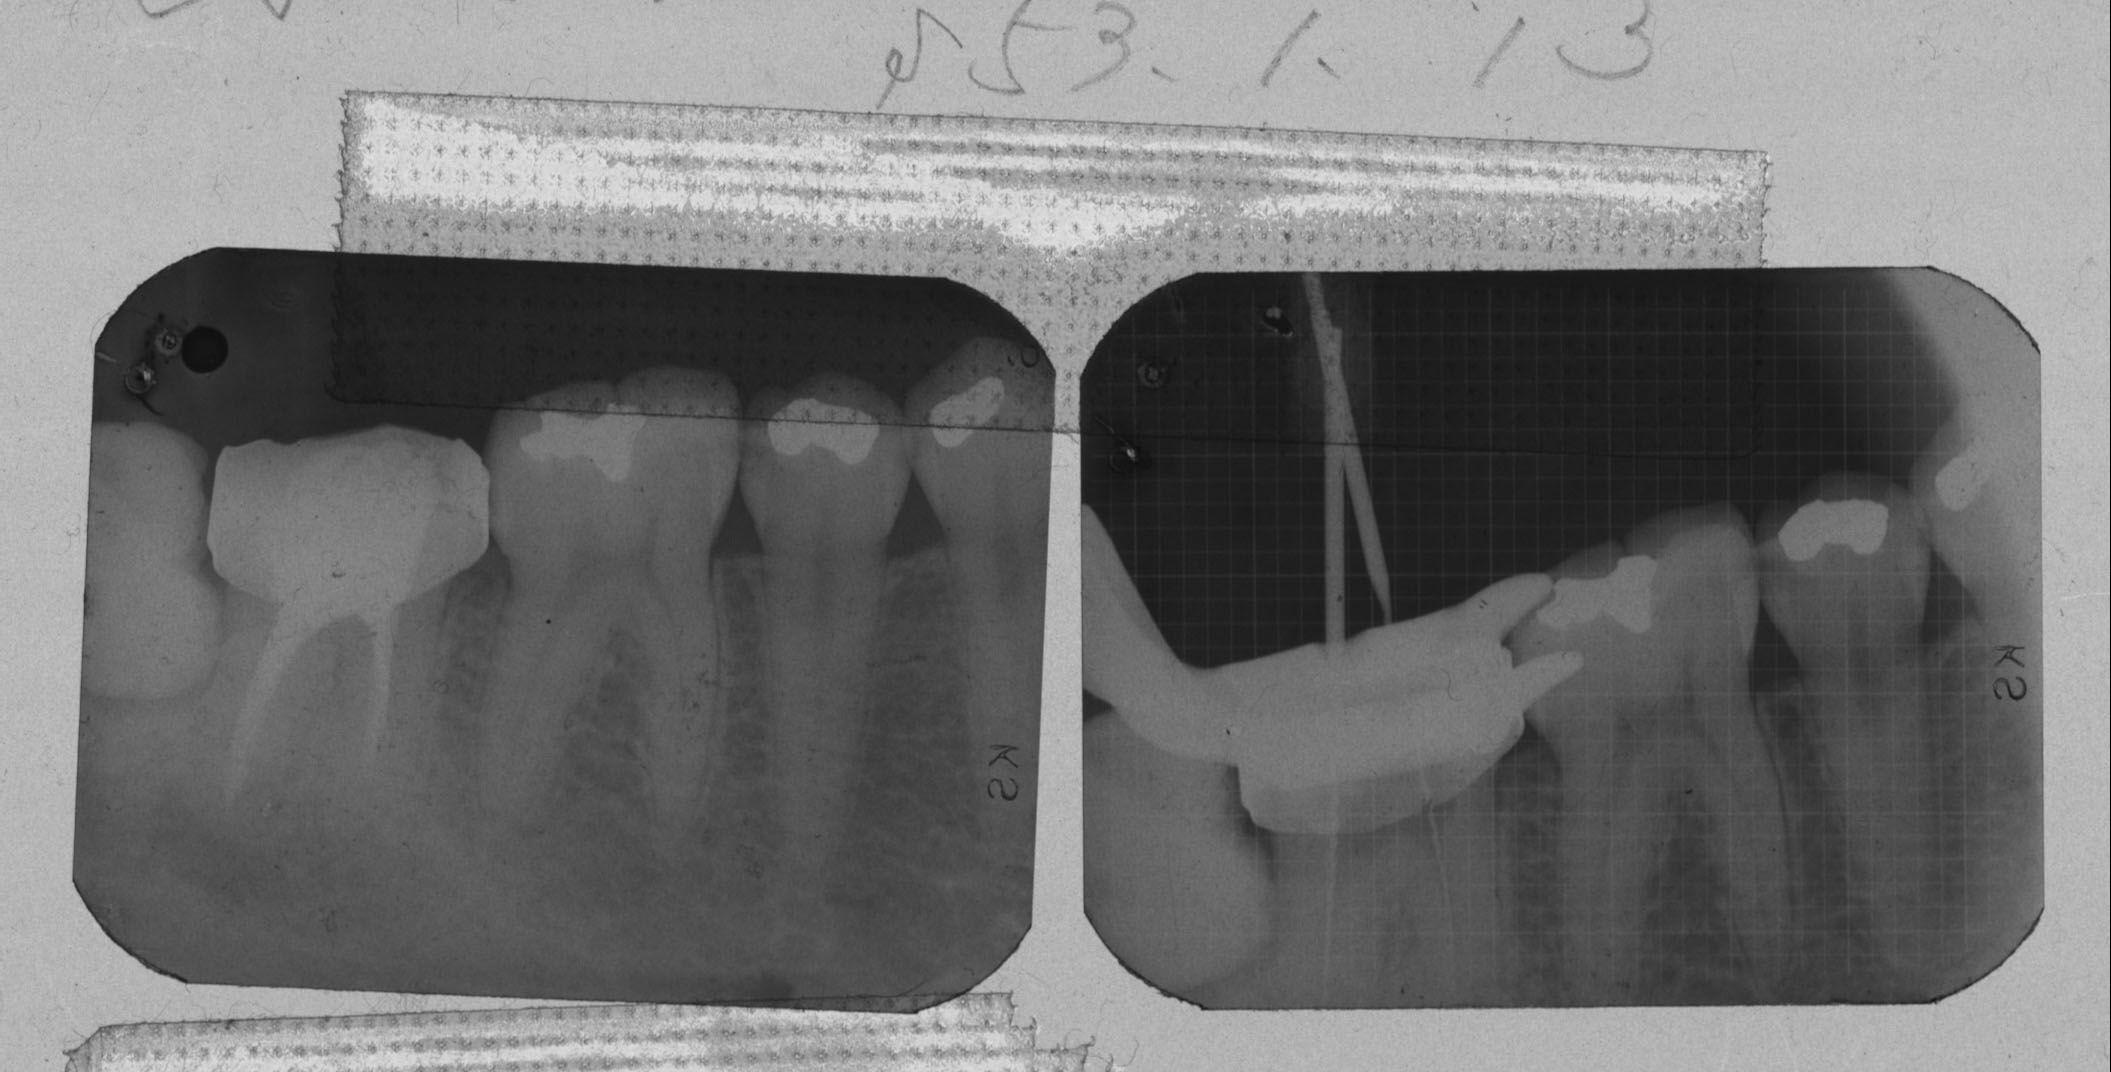

レントゲンを撮影し拝見したところ、被せ物で治療されている右下の奥歯(第2大臼歯/7番)に関して、根の先に黒い影が認められました。

細菌感染が原因で根の周りに炎症が起きる「慢性化膿性根尖性歯周炎(まんせいかのうせいこんせんせいししゅうえん)」と診断し、炎症を抑えるためには細菌感染した歯の内部の組織を取り除く治療が必要でした。

歯の神経が通っている管の中をきれいにして薬を詰める「根管治療(こんかんちりょう)」を自費で行うことをご提案しました。

歯の中がきれいになったことを確認してから、最終的な薬を詰めました。

歯の根の先の炎症の影が消えて痛み無く噛めるようになり、患者様にも大変ご満足いただきました。